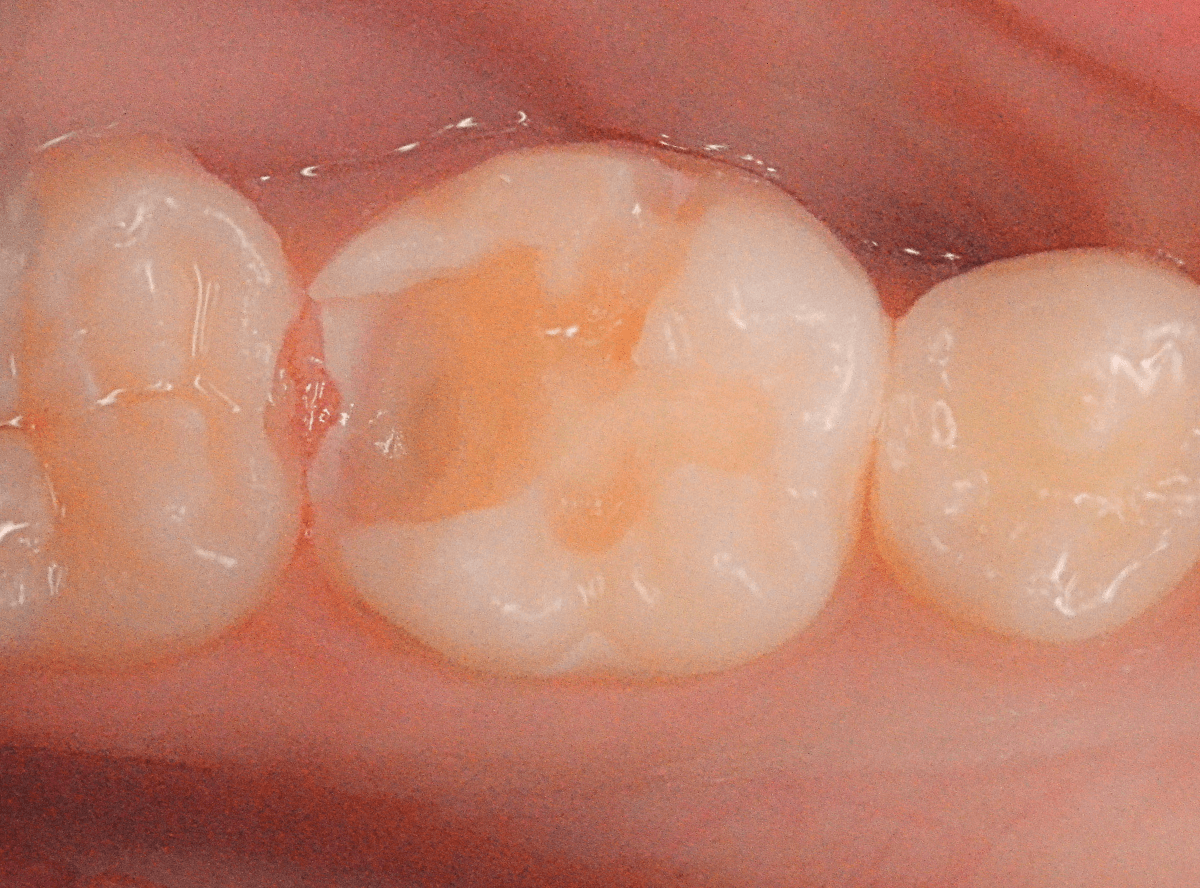

今回は、セラミックでの修復をご希望されましたので、

手前の小臼歯2本をE-MAX、

奥の大臼歯をジルコニア・インレー

で、修復する事になりました。

最終setした状態です。

大きな虫歯でしたが、治療後も特に症状もなく、見た目も満足いただける仕上がりになりました。